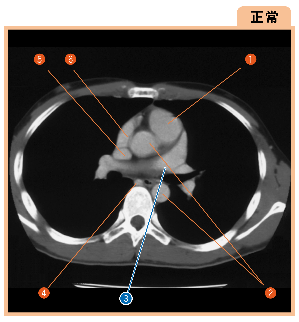

▲112ページ 正常画像内(2008/6/17)

※3の引き出し線の位置が異なっていました(下は修正済みの画像です.青線で示しています)

| ● |

|

▲112ページ(2008/6/17)

構造部位の名称中,3に誤りがございました

| × |

1 肺動脈幹(pulmonary trunk) |

1 左心耳(left auricula) |

▲112ページ(2008/6/4)

構造部位の名称中,1に誤りがございました

1 左右心室(right ventricle) |

1 右肺動脈幹(pulmonary trunk) |